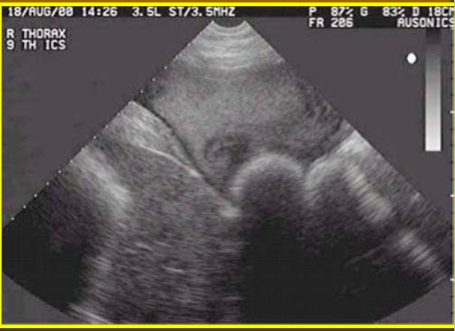

Diagnostic Test used to Confirm Cases of Diaphragmatic Hernias

Ultrasound